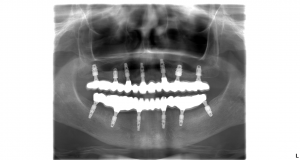

V prípade pána Tomáša bolo potrebných 6 zubných implantátov vo vrchnej a 6 zubných implantátov v spodnej čeľusti na ktoré sa nasadili 14 – členné keramické mostíky. U pni Márie bolo potrebných 7 zubných implantátov vo vrchnej čeľusti a 6 zubných implantátov v spodnej čeľusti.